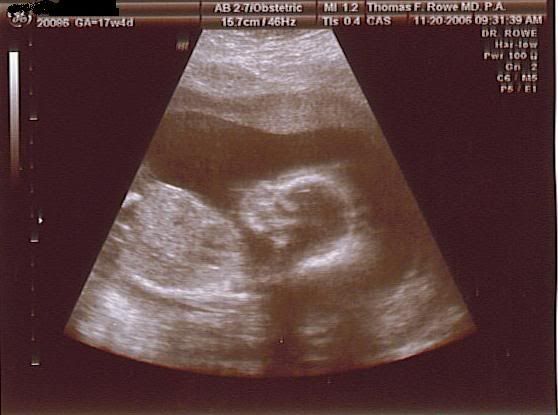

skinkybaby wrote: GIRL! We had our official ultrasound this morning and they confirmed it. I'm so excited!

They also took a look at my fibroid. The ultrasound doctor said it's about the size of an orange. Right now its even bigger than the baby's head. He said I'm probably going to have to have it surgically removed after the baby gets here. But my OB gave me some tylenol 3 and said it shouldn't cause any complications with the baby, but because of its location I am going to have to have another c-section. That's a bummer, but ya goota do what ya gotta do.